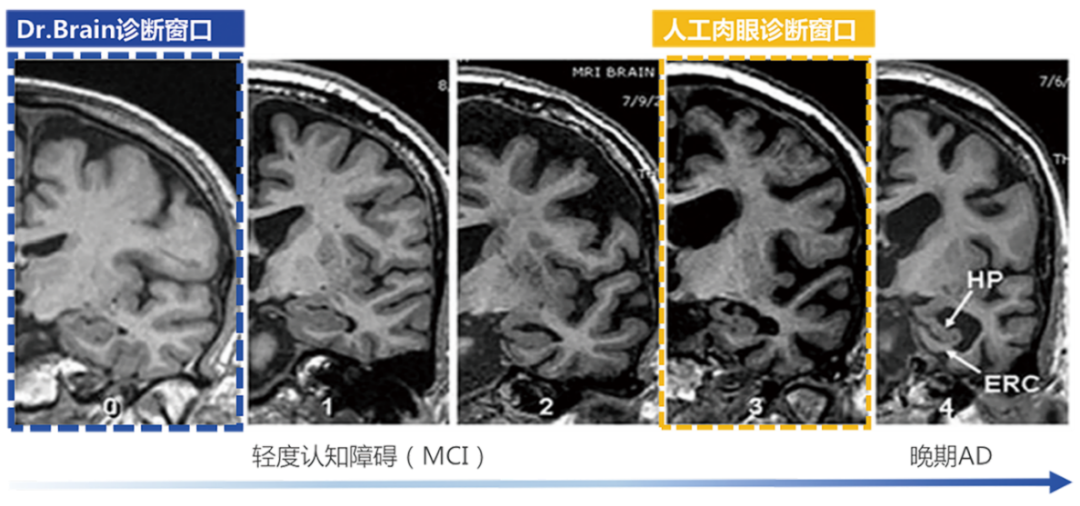

超早期的診斷

利用AI算法識別肉眼難以發(fā)現(xiàn)的腦結(jié)構(gòu)超早期的細(xì)微改變,大幅提前疾病診斷窗口

針對AD的治療,國際上已批準(zhǔn)的AD藥物基本都是對早期AD患者在延緩病程發(fā)展上有顯著療效,但對于晚期患者,即使檢出也是療效甚微?!栋柎暮D?chuàng)新藥物臨床試驗中國專家共識》強(qiáng)調(diào)AD應(yīng)著力于早期發(fā)現(xiàn)和預(yù)防,而臨床現(xiàn)狀是AD的診斷率低且漏診率高。因此,AD的早篩、早診對延緩該疾病的發(fā)展至關(guān)重要。臨床中對AD診斷首選的影像學(xué)檢查方法是磁共振成像 (Magnetic Resonance ImagingMRI) ,但臨床上大多數(shù)醫(yī)生認(rèn)為AD病人的腦結(jié)構(gòu)異常變化發(fā)生較晚,而今借助AI算法,其實醫(yī)生能在高維空間捕捉到宏觀和微觀、具體和抽象的腦結(jié)構(gòu)特征,可以輔助醫(yī)生利用MRI結(jié)構(gòu)影像在早期精準(zhǔn)診斷AD性質(zhì)的腦結(jié)構(gòu)異常改變。因此,人工智能應(yīng)用于影像診斷和疾病篩查診斷近年來變?yōu)槿蜥t(yī)療器械業(yè)界的趨勢與熱點,其中,在腦部疾病診療領(lǐng)域,即有可能改變將來的AD診療路徑。